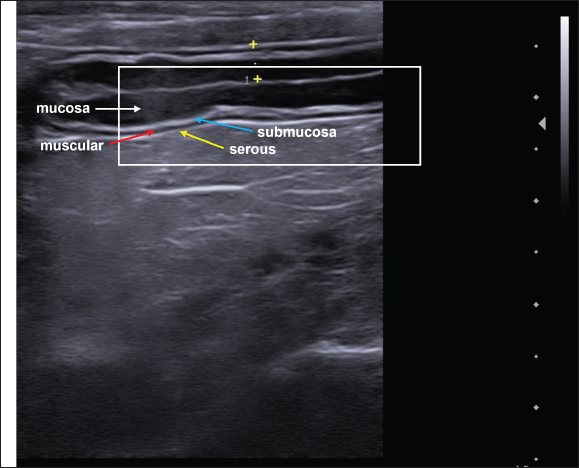

On USG, the five parietal layers can be assessed (Fig. 3), with an interface between the intestinal lumen and the mucosa that is hyperechoic and forms a bright, central line on the image. The mucosal layer is associated with this and is hypoechogenic, followed by the hyperechogenic submucosa. The thin muscular layer is hypoechogenic, and the outermost layer is the serosa, which is hyperechogenic (Goggin et al., 2000; Agut, 2009; Larson and Biller, 2009).

Fig. 3. Ultrasound image of the intestinal segments of a dog. The image shows transverse and longitudinal sections. The stratified layers are the mucosal layer (white arrow), submucosal layer (blue arrow), muscular layer (red arrow), and serosal layer (yellow arrow).